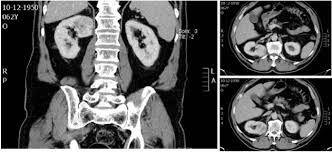

Signs Of Renal Cancer In Males : Kidney Failure Types Symptoms Causes And Treatment : Although it doesn't always draw as much attention as other types of cancer, kidney cancer is one of the 10 most common cancers, especially among people over 55.. Cancer spreads outside the kidney, to multiple lymph nodes or to distant parts of the body, such as the bones, liver or lungs. Signs and symptoms of kidney cancer. The tumor is 7 cm across or smaller and is only in the kidney. Instead, metastatic kidney cancer may cause symptoms in the newly affected areas of the body including: Each year, more than 62,000 americans are diagnosed with kidney cancer.

Symptoms of kidney cancer the most common sign of kidney cancer is blood in the urine (hematuria), which may appear rusty or dark red. People with kidney cancer may experience the following symptoms or signs. Bloody urine is typically the earliest noticeable sign of kidney cancer. The key, as is the … More frequently, the cause is smoking, says dr.

You feel the need to urinate more often. You may also experience difficult or painful urination. In addition, kidney cancer often doesn't show any obvious signs, especially in the early stages. Although it doesn't always draw as much attention as other types of cancer, kidney cancer is one of the 10 most common cancers, especially among people over 55. The risk of kidney cancer increases with age. In men, the development of a varicocele, or a clump of enlarged veins, may appear around a testicle. 97,220 new cases of colon. Dry and itchy skin can be a sign of the mineral and bone disease that often accompanies advanced kidney disease, when the kidneys are no longer able to keep the right balance of minerals and nutrients in your blood. In addition, the spread of kidney cancer to other parts of the body (metastatic disease) gives the first warning signs of the disease (such as a cough or bone pain) in 30 percent of people. Kidney cancer is cancer that begins in the kidneys. And when the gender is taken into account, it is also diagnosed more often in men than women. Instead, metastatic kidney cancer may cause symptoms in the newly affected areas of the body including: Even the slightest amount of blood will affect the color of your urine, giving it either a brown or pink discoloration.

Although it doesn't always draw as much attention as other types of cancer, kidney cancer is one of the 10 most common cancers, especially among people over 55. Blood in the urine (hematuria) low back pain on one side (not caused by injury) a mass (lump) on the side or lower back You may also experience difficult or painful urination. You may also experience difficult or painful urination. Urine may have a pinkish hue or appear dark red.

Plus, many possible kidney cancer symptoms, like blood in the urine, can also result from less. Even the slightest amount of blood will affect the color of your urine, giving it either a brown or pink discoloration. Breast lumps are relatively reliable. Tests and procedures used to diagnose kidney cancer include: It is important to note that the signs of kidney cancer are shared by many other benign (noncancerous) conditions. It is more common in men than in women. Dry and itchy skin can be a sign of the mineral and bone disease that often accompanies advanced kidney disease, when the kidneys are no longer able to keep the right balance of minerals and nutrients in your blood. Today, the most common symptoms of kidney cancer are anemia, fatigue, weight loss, loss of appetite, and a fever. In 2019, about 73,820 new cases of kidney cancer will occur. Feeling a mass on your abdomen, side, or lower back. As a rule it is painless. In addition, kidney cancer often doesn't show any obvious signs, especially in the early stages. Cancer spreads outside the kidney, to multiple lymph nodes or to distant parts of the body, such as the bones, liver or lungs.

Most symptoms have to do with your kidney function and tumor growth. Some possible signs and symptoms of kidney cancer include: There may be enough blood to change the color of the urine to orange, pink, or, less often, dark red. In addition, the spread of kidney cancer to other parts of the body (metastatic disease) gives the first warning signs of the disease (such as a cough or bone pain) in 30 percent of people. Lungs, causing cough and shortness of breath bones, resulting in bone pain or fracture brain, presenting as headaches, confusion or seizures